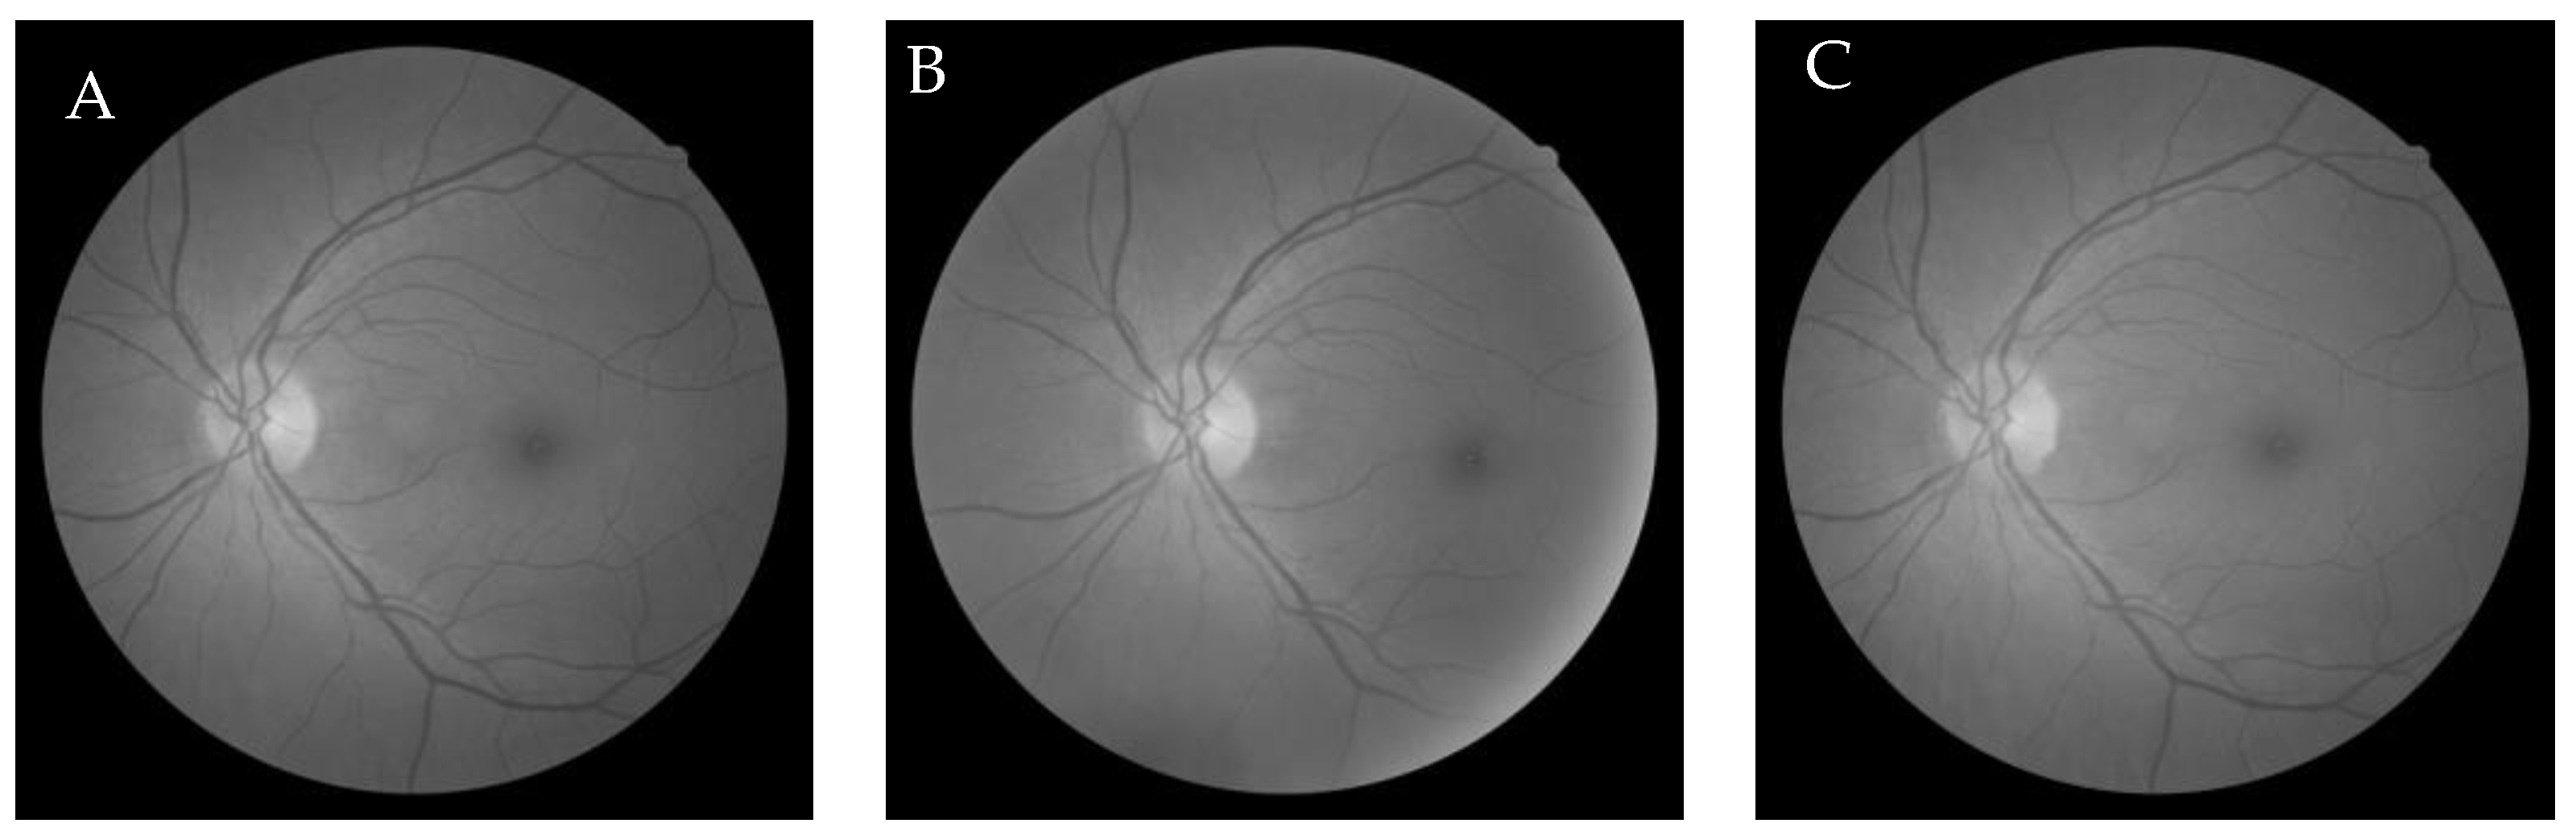

6.1. Dataset

6.2.4. Genetic Algorithm-Based Wang’s Demons Registration